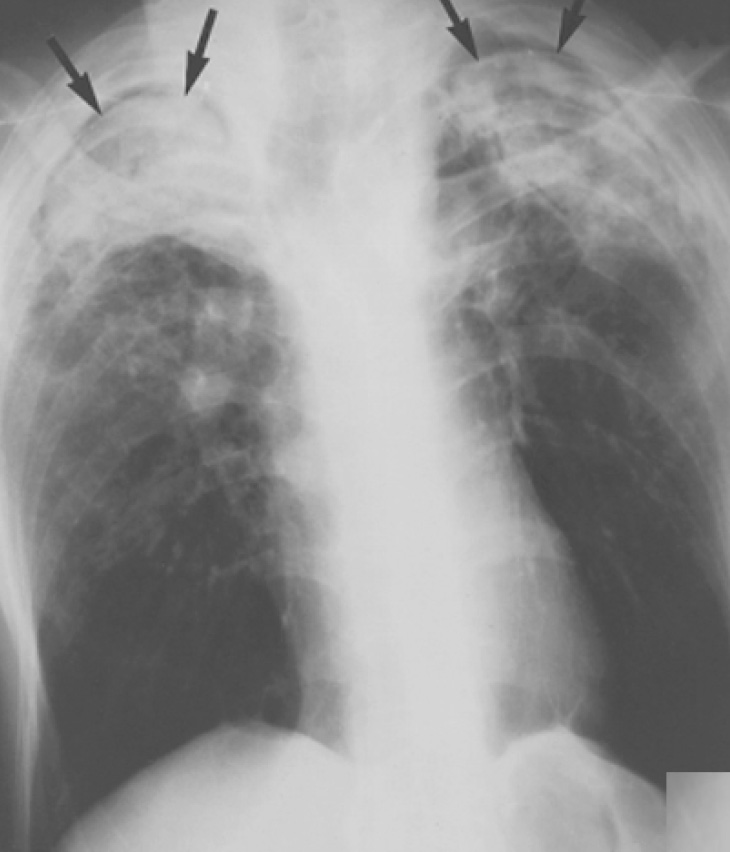

При анкилозирующем спондилоартрите в легких определяются фиброзные изменения и бронхоэктазы в верхних долях. Возможно развитие полостей в верхних долях легких, похожих на каверны – рентгенологическая картина напоминает фиброзно-кавернозный туберкулез (см статью «Рентгенография: Туберкулез легких»). также в этих полостях могут образовываться аспергилломы.

Рисунок 7. Изменения в легких у больного с болезнью Бехтерева. В обоих легких отмечается уменьшение объема верхних долей, что обусловлено фиброзом (корни легких «подтянуты» вверх). В верхних долях обоих легких видны полости с мицетомами (см стрелки)